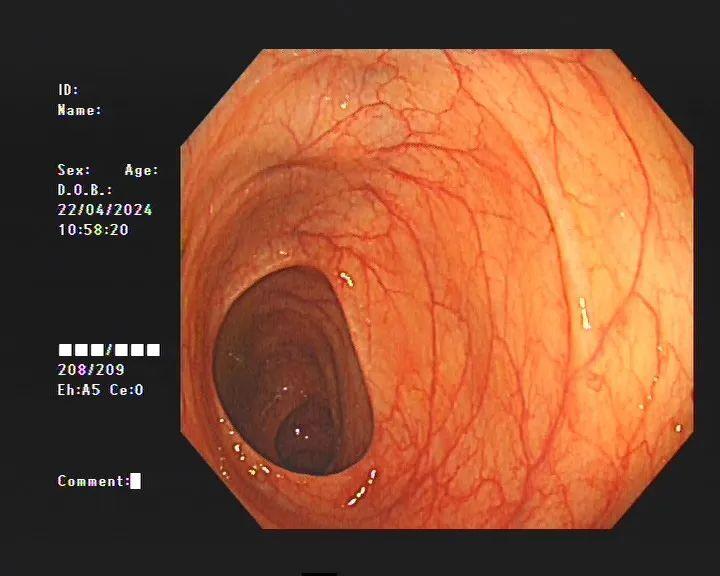

据医生介绍,临床上许多患者自行口服药物后筛查肠镜均有不同程度的结肠黑变病。正常的结肠黏膜就像我们的口腔黏膜一样,是淡红色的,看起来光滑平坦,黏膜表面的小血管纹理清晰可见。而结肠黑变病的肠黏膜色泽呈现棕色、褐色,有豹纹或者蛇皮一样的条状纹,严重的甚至会变成黑色。

正常的肠道